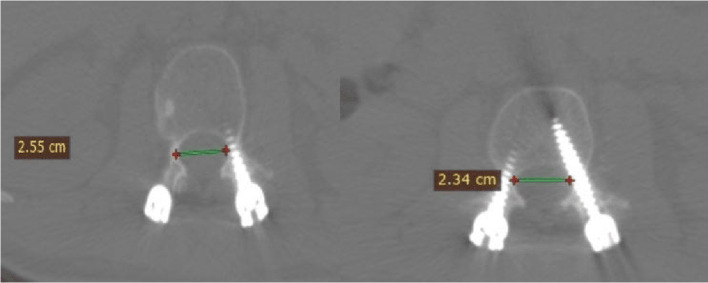

Objectives: Our study aimed to evaluate the reliability and validity of the use of a new scoring system (the Meshtawy Pedicular Screw Malposition - MPSM) for evaluating pedicle screw misplacement by a detailed clinical-radiographic comprehensive scoring system (MPSM) with sharp guidance for treating injurious violations by assessing the correlation between the neurological data of patients and computed tomography (CT) findings.

Patients and methods: This prospective case series included 100 patients (508 pedicular screws) who underwent transpedicular fixation at Orthopedic department Al-Azhar University Hospital, Assiut branch, Egypt 255 (50.2%) screws were inserted on the right side, while 253 (49.8%) were inserted on the left side. Intra-observer reliability was examined by calculating Cronbach's alpha intraclass correlation coefficient, which compares three measurements obtained by each observer at different time points. Inter-observer reliability was also examined by calculating Cronbach's alpha intraclass correlation coefficient and comparing the average measurements obtained by each observer.